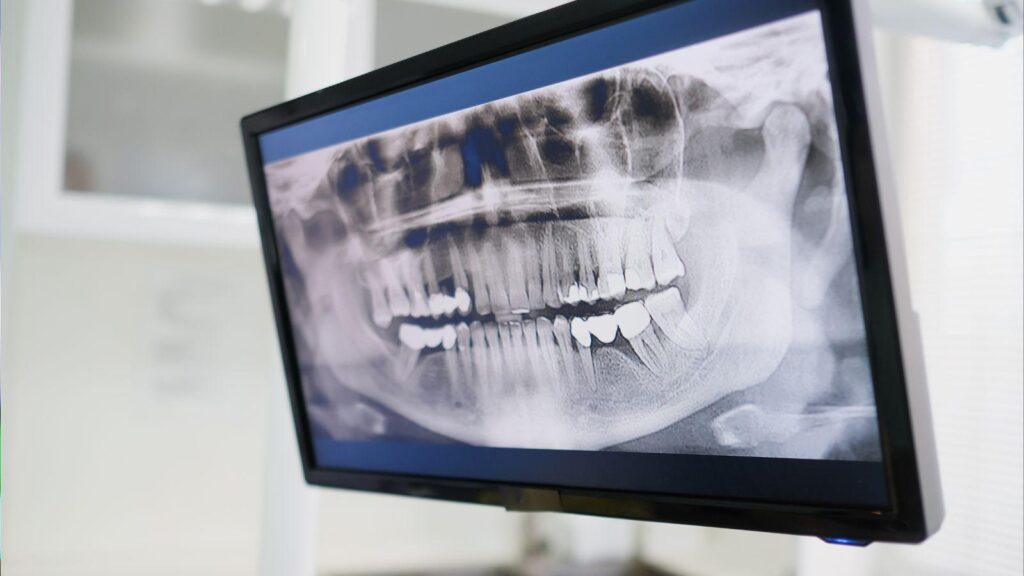

Panoramic Radiograph

A panoramic radiograph gives a wide view of your jaws, teeth, and sinuses in one image. It shows overall bone height and major anatomical landmarks, like the mandibular canal and maxillary sinuses, so your dentist can spot large problems or missing bone.

This image uses low radiation and is quick to take. It helps plan whether simple implants are possible and flags areas needing more detailed scans. Panoramic films do not show fine bone detail or exact thickness, so they’re often a first step rather than the only test.